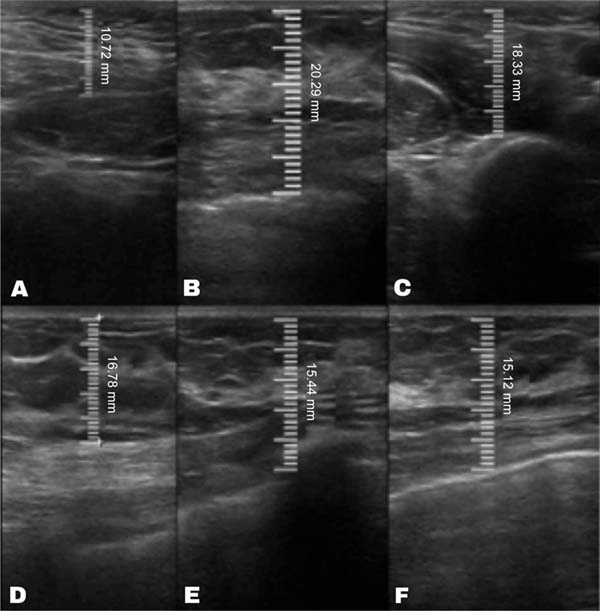

The measurement of subcutaneous tissue thickness is performed vertically, from the highest (right at the transition from the epidermis) to the lowest point (at the transition with the muscle tissue) of subcutaneous tissue thickness. This measurement is easily reproducible for those with basic ultrasound skills (►Fig. 2). In lipofilled breasts, the thickness of subcutaneous tissue was measured preoperatively and immediately after lipofilling, as well as at 15, 30, 90, and 180 days postoperatively. Measurements in millimeters were taken using ultrasound, including the vertical distance from the highest (closest to the epidermis) to the lowest point (closest to the adjacent musculature) of the subcutaneous tissue at the previously defined point. A GE LOGIQ P6 (GE HealthCare) ultrasound device with an 11L linear probe and a frequency range of 12 to 6 MHz was used, operated by a surgeon with postgraduate training in general ultrasonography (►Fig. 3).

In the decanted graft group, the average reduction compared with the initial thickness after lipofilling was 9.90% on day 15, 19.27% on month 1, 23.59% on month 3, and 26.36% on month 6. In the filtered graft group, the average reduction compared to the initial thickness after lipofilling was 7.74% on day 15, 14.85% on month 1, 20.67% on month 3, and 22.80% on month 6 (►Fig. 6). ►Figs 7–8 reveal the ultrasound change in subcutaneous tissue’s thickness before and after lipofilling. ►Figs. 9–10 show the pre-and postoperative results of one patient from each group.